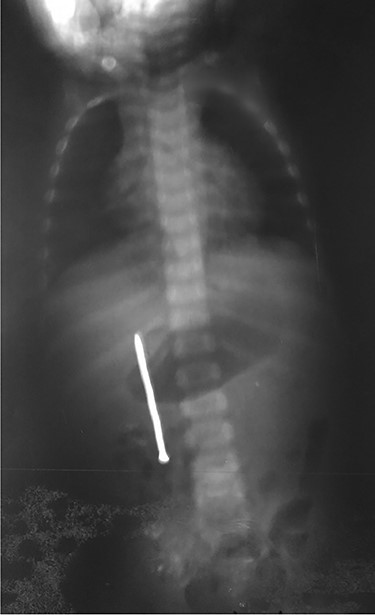

Abdominal examination was normal. A repeat abdominal radiography was done. The nail’s position had not changed from the first X-ray site, with no free peritoneal air (Fig. 2).

In our case, according to the nail’s position on abdominal radiography, perforations were probably due to duodenal wall extension and progressive erosion of the nail’s head through the duodenal wall [3–5]. Our patient did not present signs of peritonitis neither free peritoneal air (pneumoperitoneum) because the site of duodenal perforation was covered by adjacent loops of ascending colon. This avoids the passage of intraluminal air into the peritoneal cavity.

Plain radiography plays the main role both in the diagnosis and the choice of operative interventional moment—either by pinpointing the radio-opaque image, or by showing certain FB characteristics, or by noting images suggesting complications (absent in our case), or even by projecting the FB in the same place over a period of time, an aspect inductive of fistula. In our case, right-edge superposition of the FB image upon the lumbar spine is characteristic of FB positioning in the second part of duodenum [5, 6]. Its persistence in the same place (the second part of the duodenum as in our case) suggests the presence of a duodenal fistula or perforation, which requires surgical intervention [7].